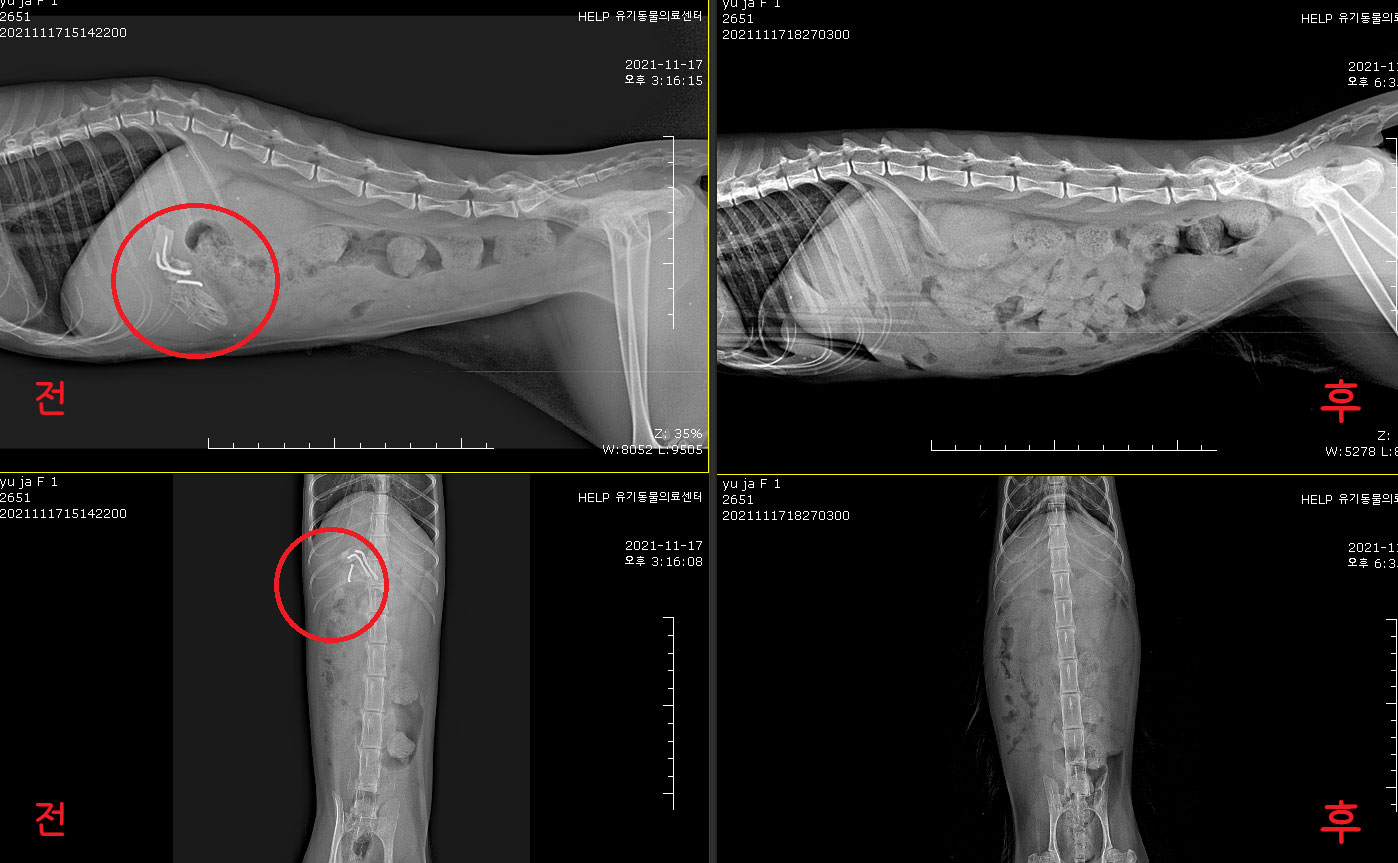

Áï½Ã Ÿ º´¿ø¿¡¼­ X-ray ÃÔ¿µÇß°í,

±Ý¼Ó ¹× ¾Ë ¼ö ¾ø´Â ³Îµû¶õ ÇüÅÂÀÇ ¹°Ã¼°¡ À§ ³»¿¡¼­ ¹ß°ßµÇ¾ú¾î.

¼ö¼ú Àü X-ray ÀçÃÔ¿µ Çߴµ¥, ¿©ÀüÈ÷ À§ ³»¿¡ ÀÖ´Â °ÍÀ¸·Î È®ÀεǾú¾î.

¼ö¼ú ÈÄ ´Ù½Ã Çѹø X-ray ÃÔ¿µÇÏ¿©, À§³» À̹°ÀÌ ³²Áö ¾ÊÀº °Íµµ È®ÀÎÇß¾î!

£¨¼ö¼ú Àü ÈÄ£©